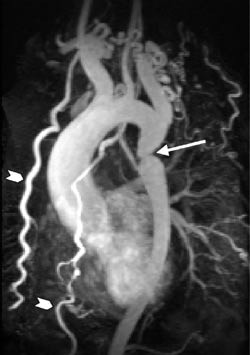

En sentral problemstilling ved iskemisk hjertesykdom er differensieringen mellom viabelt og ikke-viabelt myokard. Man har brukt flere strategier for å skille mellom disse tilstandene med MR (11). Såkalt stresstest med lavdose dobutamin blir oftest utført med ekkokardiografi, men kan også gjøres med MR. Den beste MR-metoden for diagnostisering av ikke-viabelt myokard har imidlertid vist seg å være påvisning av forsinket kontrastopptak (fig 2). 10 – 20 minutter etter intravenøs injeksjon av et ekstracellulært MR-kontrastmiddel vil man ved hjelp av spesielle bildeopptak («viabilitetsopptak») se kraftig kontrastoppladning i både nye og gamle infarkter, men ingen oppladning i levende myokard (12). Inntil nylig var påvisning av glukosemetabolisme med positronemisjonstomografi (PET) gullstandard i differensieringen mellom viabelt og ikke-viabelt myokard. Viabilitetsopptak med MR er en like sensitiv metode, men romoppløsningen er bedre. I motsetning til PET kan MR også vise den transmurale utbredelsen av et infarkt. Kliniske studier har vist at sannsynligheten for funksjonell bedring etter revaskularisering er nøye relatert til hvor stor del av veggtykkelsen som er infarsert. De aller fleste veggsegmentene som viser mindre enn 50 % transmural infarsering vil bedre sin kontraksjonsevne etter revaskularisering (13).